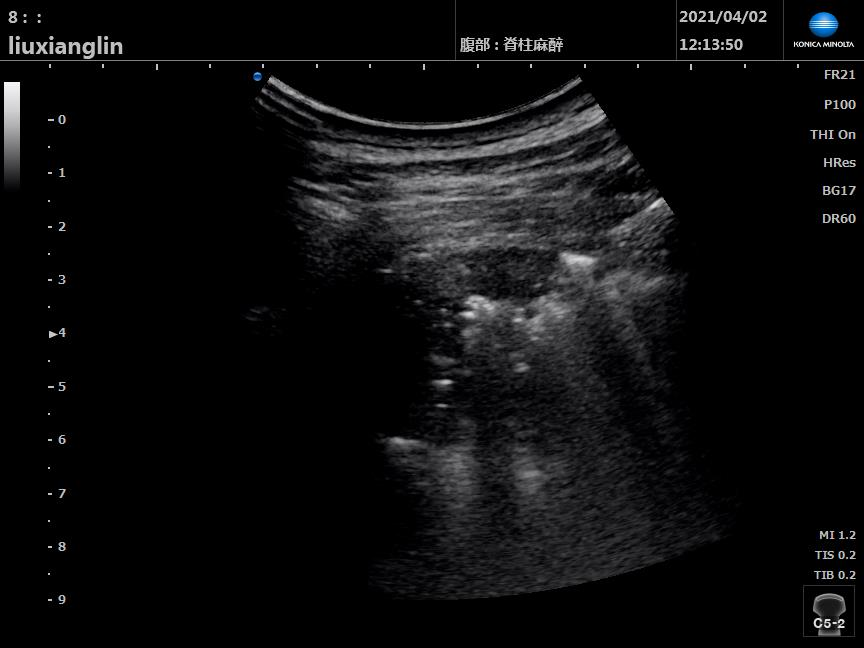

▲超声实时监测 灌洗侧肺超声声像可见“肺间质综合征→肺水肿→肺实变”